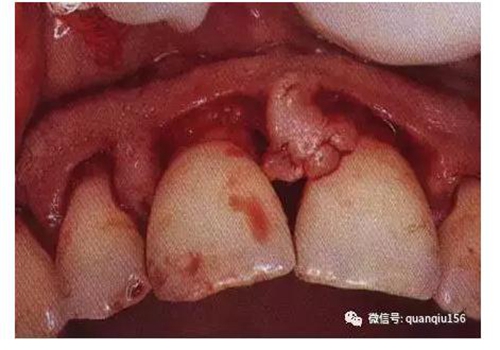

一般在距齦緣1~2mm處進(jìn)刀,切向根方,直達(dá)牙槽嵴頂或其附近。刀片與牙而成10°角左右,以提插方式移動,每次插入均達(dá)骨嵴頂。沿著牙的齦緣外形作切口,保留齦乳頭的外形,避免切除齦乳頭,最終形成扇貝形的牙齦外形。切口完成后,袋內(nèi)壁的上皮和炎癥肉芽組織、結(jié)合上皮、袋底與骨嵴頂之間的結(jié)締組織纖維與齦瓣分離,仍包繞著牙齒,有待第二切口、第三切口將其徹底清除。

內(nèi)斜切口是翻瓣術(shù)中最關(guān)鍵的切口,也是目前采用最多的切口。其優(yōu)點(diǎn)是:將袋內(nèi)壁的上皮和炎癥組織切除;保留相對完好的袋外側(cè)面的角化齦;形成的齦瓣邊緣薄,易于貼附牙面和骨面,愈合后牙齦外形良好。